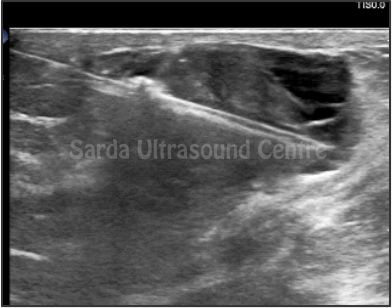

Our facility offers comprehensive range of ultrasound-guided interventions such as FNAC, biopsies, injections and aspirations, ensuring precise and safe treatment for our patients.

With Detailed pre-procedure councelling, High resolution ultrasound machines, Significant experience in using ultrasound for guided procedures, maintainance of sterile environment ensuring highest level of safety; we are committed to providing the highest standard of care for all ultrasound guided interventions.